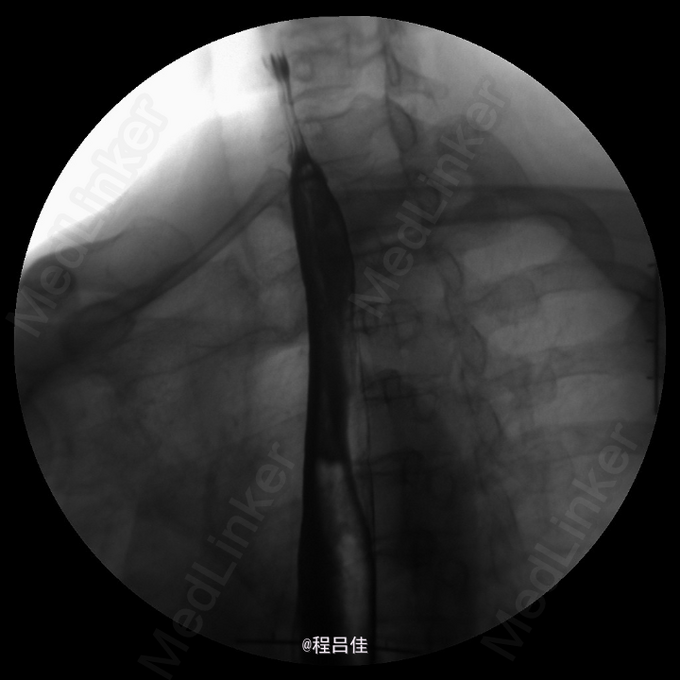

查体:T 36.4℃,P 80次/分,R 13次/分,BP 110/78mmHg。心肺腹阴性。 辅查: 常规胸透示食管:对比剂通过顺畅;食管胃环上提,并可见一浅切迹影,膈上见胃黏膜影,立位时消失。余食管未见明确狭窄、扩张现象,管壁光整,柔软,舒缩功能良好,黏膜皱襞排列规则,未见明确增粗、紊乱、中断现象,未见明确龛影及充盈缺损影;可见少量胃食管返流;球后部扩张,黏膜增粗,扩张以下肠管稍狭窄,但肠壁黏膜规整、柔软,未见明确充盈缺损。结论1.考虑滑动性食管裂孔疝。 2.十二指肠球后部局部稍变窄,黏膜增粗,建议进一步肠镜检查。 3.轻度胃食管返流。